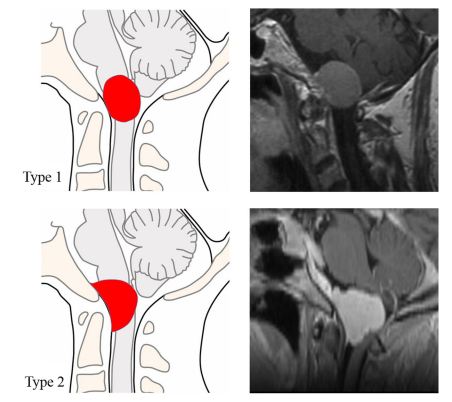

圖3圖(左)和T1加權(quán)磁共振圖像的兩個(gè)治療病例(右)描繪了兩種類型的矢狀硬腦膜附著。我們將矢狀位硬腦膜附著長(zhǎng)度/較大顱尾徑之比<1的腫瘤描述為Btype 1,而比率≥1的Btype2^